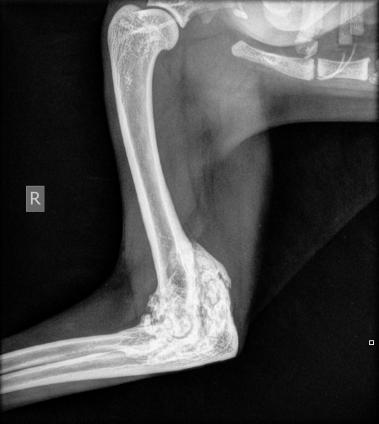

Durch die klinischen Symptome, den Bericht des Besitzers und unter Berücksichtigung des Alters hat Ihr Tierarzt häufig schon einen starken Verdacht. Dieser lässt sich durch die Röntgendiagnostik bestätigen und liefert Hinweise auf den Schweregrad der Erkrankung.

Eine gezielte Röntgenuntersuchung zeigt in der Regel das Ausmass der Arthrose in den betroffenen Gelenken. Leider sind diese Veränderungen nicht heilbar. Das Ziel einer Therapie ist die Verminderung der Schmerzen und die Verbesserung der Gelenkbeweglichkeit.